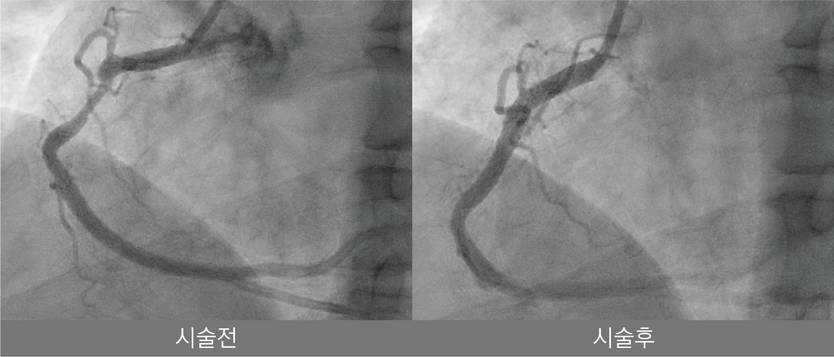

해당 시술은 심장내과 안태훈 원장과 한동훈 과장이 주도했으며 48세 남성 환자를 대상으로 시행됐다. 환자는 약 5개월 전부터 운동 시 흉통 증상이 반복적으로 나타나 나은병원을 찾았으며 관상동맥 조영술과 혈관내 초음파 검사 결과 우관상동맥 기시부에 심한 석회화를 동반한 병변이 확인됐다. 의료진은 기존 치료만으로는 충분한 확장이 어렵다고 판단해 혈관 내 쇄석술을 적용하기로 결정했다.

혈관 내 쇄석술은 특수 풍선 카테터를 혈관 내부에 삽입한 뒤 저강도 충격파를 전달해 혈관 벽에 단단히 굳은 석회 성분을 미세하게 균열시키는 최신 중재 시술이다. 이를 통해 병변의 탄력성을 개선하고 스텐트를 보다 균일하고 안정적으로 확장할 수 있어, 기존 치료법인 고압 풍선 확장이나 회전 죽종절제술에서 우려됐던 혈관 손상 위험을 줄일 수 있는 것이 특징이다.